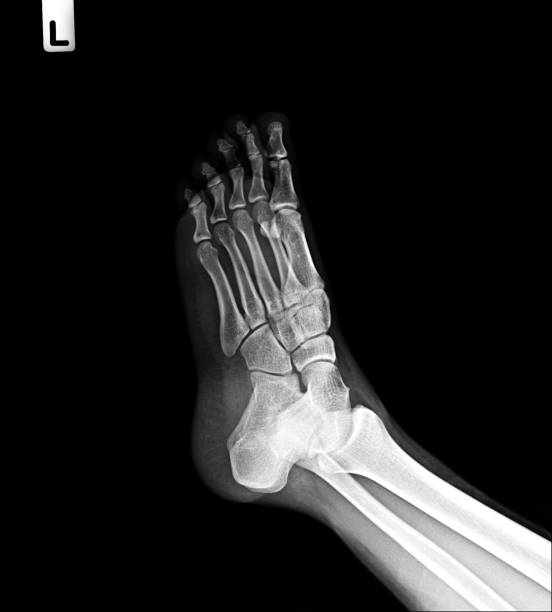

What Is a 5th Metatarsal Fracture?

This injury involves a break in the long bone on the outside of your foot.

It’s common in athletes due to:

- rolling the foot inward

- sudden direction changes

- awkward landings

- repetitive stress

What Is a Lisfranc Injury?

A Lisfranc injury affects the midfoot and can involve ligaments, bones, or both.

These are less common — but more serious.